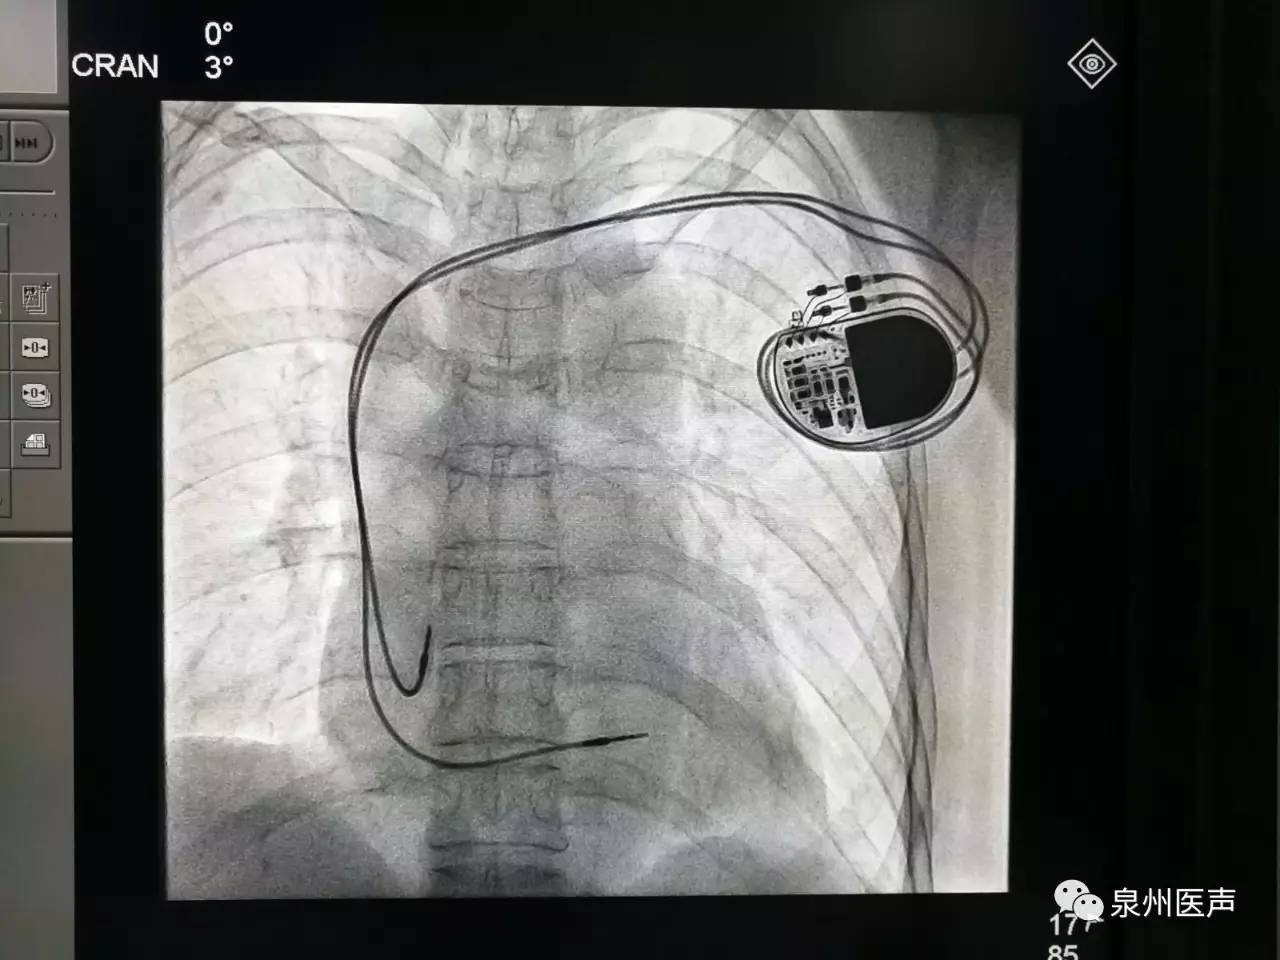

全球唯一!無(wú)線雙腔起搏器首次植入

來(lái)源:器械之家,未經(jīng)授權(quán)不得以任何形式轉(zhuǎn)載,且24小時(shí)后方可轉(zhuǎn)載。2022年2月7日雅培宣布,其在研型Aveir?雙腔無(wú)引線起搏器完成了全球首例患者植入,這也是全世界第一個(gè)雙腔無(wú)線起搏器。Aveir?DR雙腔起搏器提供右心房和心臟右心室的同步、逐次跳起搏,近80%接受起搏器治療的患者需要雙腔選擇,A